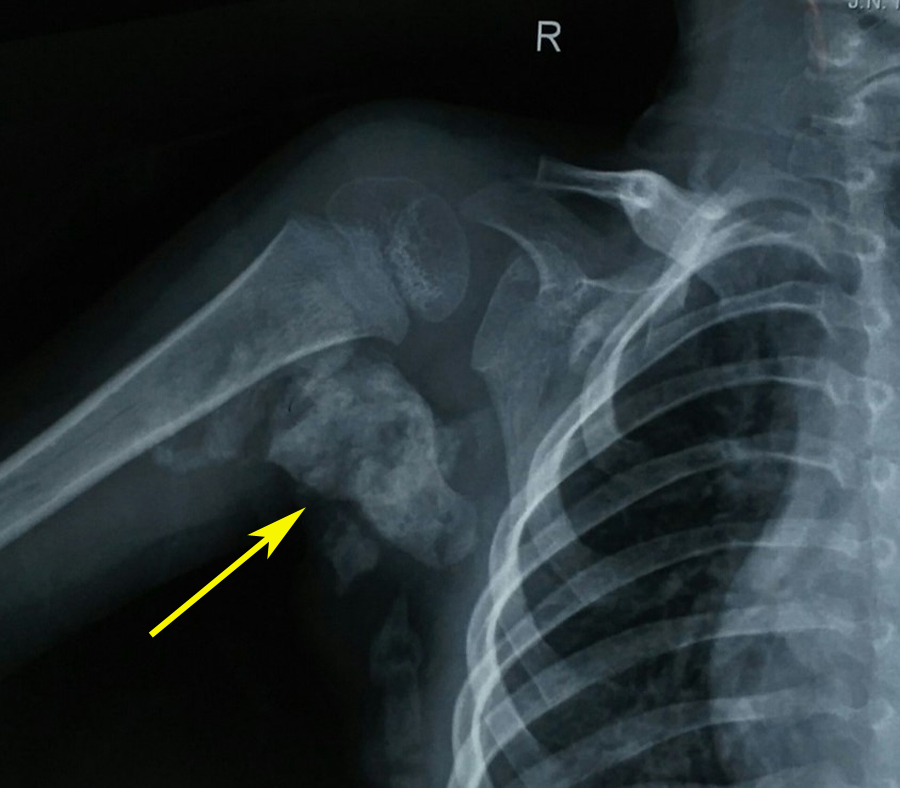

Physical examination revealed bilateral shortening and valgus deformity of the great toes (Figure 1). Multiple swellings of variable size were present on occiput, nape of neck, bilateral scapular area, bilateral axilla and midback. Swellings were non tender, hard, smooth, mobile with well-defined edges and were lying in subcutaneous tissues & muscles. Movements of the neck and bilateral shoulder were decreased (Figure 3). Rest of the joints including bilateral hips, elbows, wrists, knee, and ankle were normal. A radiograph of the right shoulder showed osteomas between the scapula and the proximal end of the humerus (Figure 4). Cervical spine radiographs revealed large posterior elements, narrow vertebral bodies and loss of cervical lordosis (Figure 5). Radiograph of the dorso-lumbar spine revealed large ectopic bone mass bridging the lower dorsal and lumbar spine (Figure 6). Radiograph of the knees revealed the presence of osteochondromas of the proximal medial end of the tibia (Figure 7). Lab findings were normal except for raised ESR (50mm in first hour) & liver enzymes were mildly raised. Patient was diagnosed as a case of FOP on the basis of clinico-radiological examinations. Biopsy was not done because of the fear of flaring up of the disease. Oral prednisolone was given in a dose of 2mg/kg for 5 days. Acute flare of the disease settled and the patient was discharged with advice of regular follow-ups.

Figure 4 A radiograph of the right shoulder showed variable sized osteomas (arrow) with calcifications between the scapula and the proximal end of the humerus.

While some flare-ups spontaneously regress, flare-ups can transform soft tissues (skeletal muscles, tendons, ligaments, fascia, and aponeuroses) into heterotopic bone. Newly formed bone (Figure 4 & 6) spans the joints, renders movement impossible.5,14 The natural history of this condition is characterized by inflammatory episodes of 2 to 3 weeks, with latency periods of several months in between. Ectopic skeletogenesis follows a specific anatomic configuration, involving the dorsal, axial, cranial, and proximal regions of the body first, followed by involvement of ventral, appendicular, caudal and distal regions later.1,6 The most common site for the onset of heterotopic ossification is the neck, with the spine and shoulder girdle being the next most common sites.1,4,6 Though heterotopic ossification in fibrodysplasia ossificans progressiva begins in childhood; but trauma such as minor soft tissue injury, muscular stretching, overexertion and fatigue, intramuscular injections and influenza-like illnesses can persuade flare-ups of the disorder. Loss of movements is accumulative and most patients are wheelchair bound by the end of the second decade. However, diaphragm, tongue, cardiac muscles, smooth muscles and extra-ocular muscles are spared from abnormal ossification.